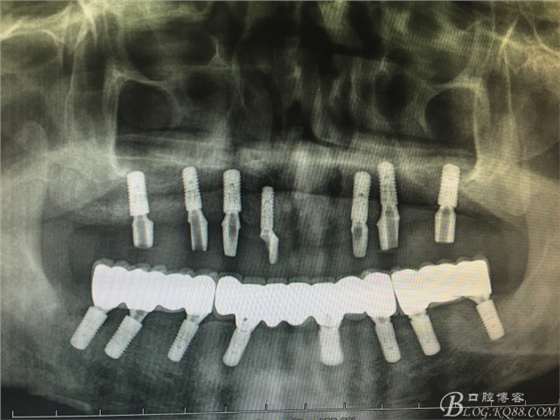

患者37歲 男 全口牙周病 手術(shù)一次完成 全程3小時(shí)全口種植修復(fù)全口種植修復(fù)全口種植修復(fù)全口種植修復(fù)全口種植修復(fù)全口種植修復(fù)全口種植修復(fù)全口種植修復(fù)全口種植修復(fù)全口種植修復(fù)全口種植修復(fù)全口種植修復(fù)全口種植修復(fù)全口種植修復(fù)全口種植修復(fù)